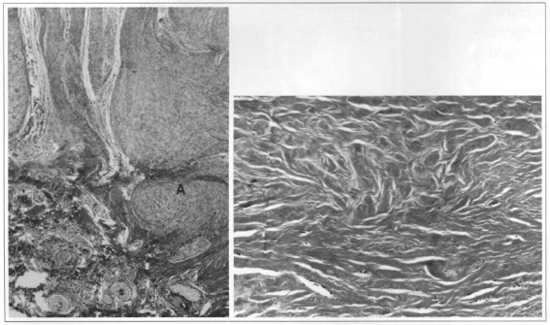

The optical microscopy findings(7,16), observed in the specimens before bleomycin sulfate infiltrations, are grouped as follows in Table II & Figs. 1a and 2a.

Fig. 1 - a) Before treatment, observe the nodular arrangement of collagen fibers (A). Gomori stains (x40). b) After use of bleomycin, note marked hypocellularity, hyalinization and disorganization of connective tissue in the central part of the keloid. Gomori stains (x100).

After infiltrations, the histopathological aspects were observed in Table III & Figs.1b and 2b.

Fig. 2a - Before use of bleomycin. b) After treatment, observe marked reduction in mucopolysaccharides and modified fibrous tissue proliferarive partern. Colloidal iron staining (x400).

The histopathological findings of biopsies performed before the infiltrations with bleomycin sulfate demonstrated results similar to those reported by other authors(14,16,18). Therefore, granulation tissue collagen fibers are arranged in hyalin bundles in normal scar. Unlike, in keloids, they present a nodular partem until they become thick bundles, compacted and hyalinized. When the collagen condensation nodule is in the papillar dermis, the epidermis may be elevated. Mature keloids have markedly thick and hypereosinophilic collagen bundles, with few elastic fibers and structures.

In 9 (60%) patients, volume reduction of keloidal scar after bleomycin sulfate infiltrations coincided with the histopathological findings of modified nodular pattern, which is characteristic of these lesions and was observed, before treatment, in all 15 patients studied.

Hypocellularity especially identified by absent nuclei, marked hyalinization of collagen bundles, absent elastic and reticular fibers in 100% of the cases, reduced interstitial acid mucopolysaccharides, as well as modified proliferative pattern of fibrous tissue in nine cases, are morphological evidences of the major alteration produced in the structural aspect of the lesions after treatment. Moreover, they correlate with softening of hardened texture, usually observed in these lesions.